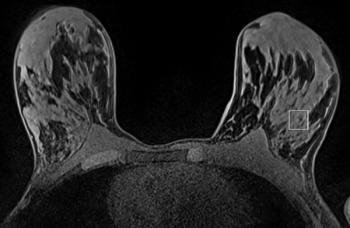

Case History: 67-year-old female with progressive increase in size of left breast for five years.